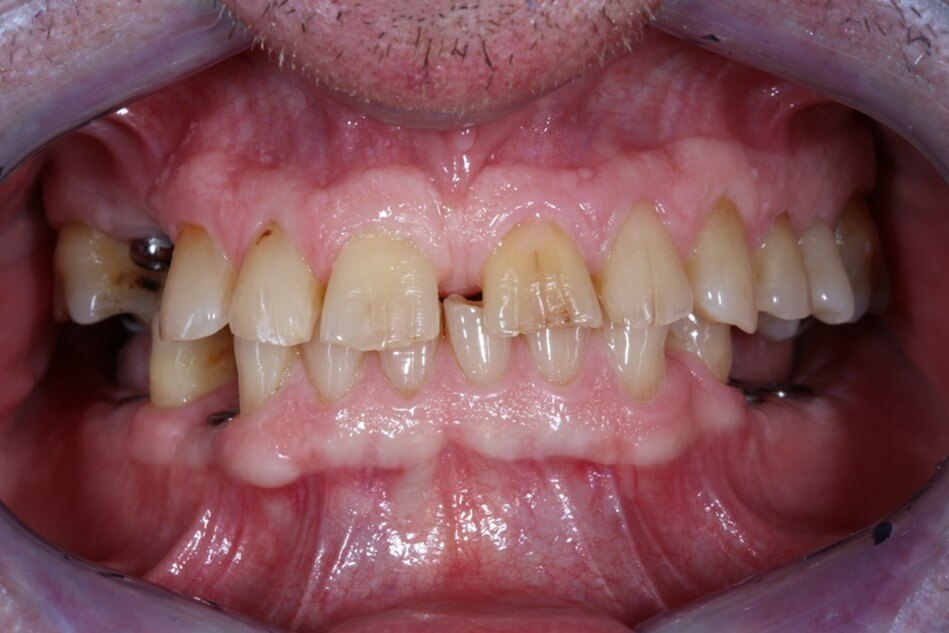

- Τα δόντια έχουν υποστεί έντονη φθορά ή έχουν χαθεί λόγω εκτεταμένων τερηδόνων, περιοδοντικής νόσου ή τραύματος.

- Τα δόντια έχουν φθαρεί και έχουν χάσει τα χαρακτηριστικά τους (σχήμα, μέγεθος) λόγω διάβρωσης από οξέα (τρόφιμα, ποτά, γαστροοισοφαγική παλινδρόμηση) ή χρόνιου βρυγμού.

- Υπάρχουν πολυάριθμες προσθετικές αποκαταστάσεις που χρειάζονται αντικατάσταση.

Κλινικές Περιπτώσεις